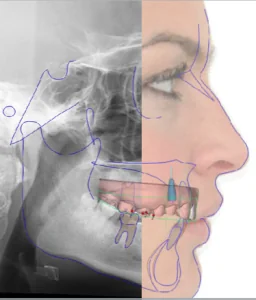

CT种植设计